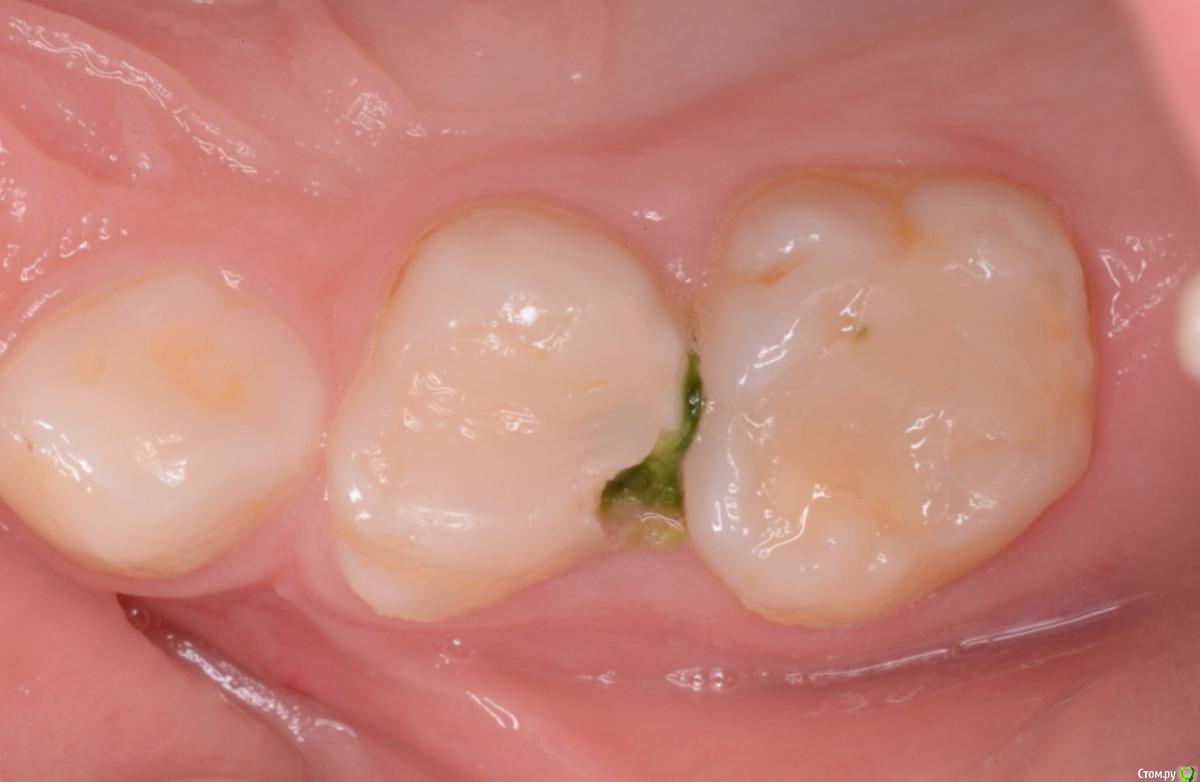

CRAZYDUCK Опубликовано 30 мая, 2018 Автор Поделиться Опубликовано 30 мая, 2018 Лечение 7.4 . Необратимый пульпит 7.4 зуба . В данном случае хорошо видно , что после ампутации гемостаз не наступает ( полость зуба заполнена кровью). Позже выложу случай со спонтанным гемостазом . Одного критерия , который бы со 100% вероятностью помогал понять , что нужна экстирпация нет . ❗Жалобы —если была самопроизвольная боль , которая не была связана с приемом пищи или выраженное последействие после пищи, боль купировалась приемом обезболивающего . Болит так , что ребёнок плачет . Самопроизвольная боль есть - скорее всего экстирпация ( если не удаление зуба).❗RVG если полость пульпы сообщается с кариозной полостью , то скорее всего экстирпация - учитывать проекцию тоже нужно .❗Гемостаз должен наступить через 4-5 минут после ампутации, если его нет - экстирпация .В данном случае боль была только кратковременная после приёма жесткой пищи . Преп, экстирпация ( Sxмашинный протейпер ), потом до 25.02 ручными , гипохлорит 3%, Йодотин в каналы , IRM культя , коронка фиксирована на Айрекс Цем . Обратите внимание - во время обработки зуба под Коронку - все в хлам и платок и десна . Предупреждаем родителей о дискомфорте , связанном с травмированием десны. 7 Ссылка на комментарий